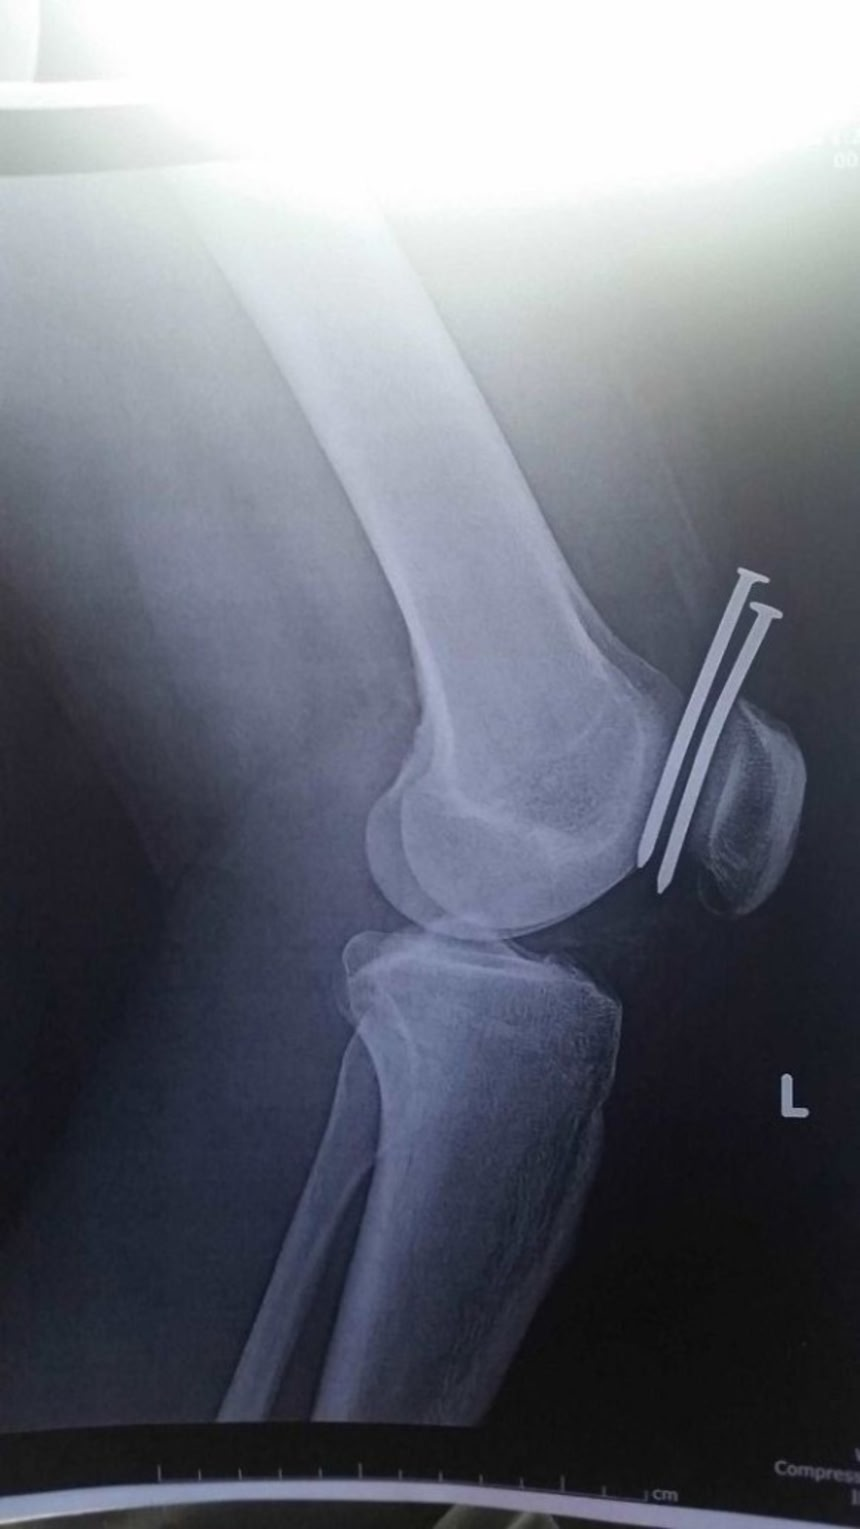

この画像を大きなサイズで見る13. 運悪く膝に釘が刺さった男性。でも大腿骨と膝蓋骨は無事だった!